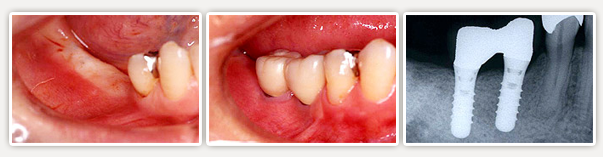

【インプラントの治療事例】

片側の奥歯が無くなった場合

【術前】

右下奥の歯は虫歯を放置していたためにぼろぼろです。残念ながら抜歯をしました。。

【術後】

インプラント治療を行いました。両隣の歯を削らずにすみました。新しい自分の歯のようで違和感も無いので大変喜ばれました。

- インプラント治療(2本)

- 上部セラミック冠